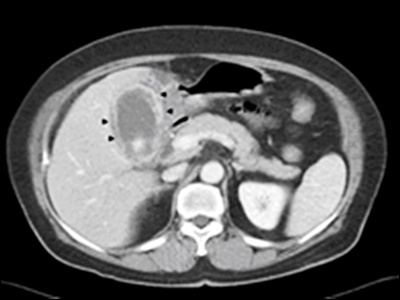

의사는 담낭염을 진단하기 위해 다양한 검사를 시행할 수 있습니다. 가장 일반적인 검사는 혈액 검사와 초음파 검사입니다. 혈액 검사를 통해 염증 마커나 감염 여부를 확인할 수 있으며, 초음파 검사를 통해 담낭의 상태와 담석의 유무를 확인할 수 있습니다. 추가적으로 담도 조영술, CT 스캔, MRI 등의 검사도 시행될 수 있습니다.